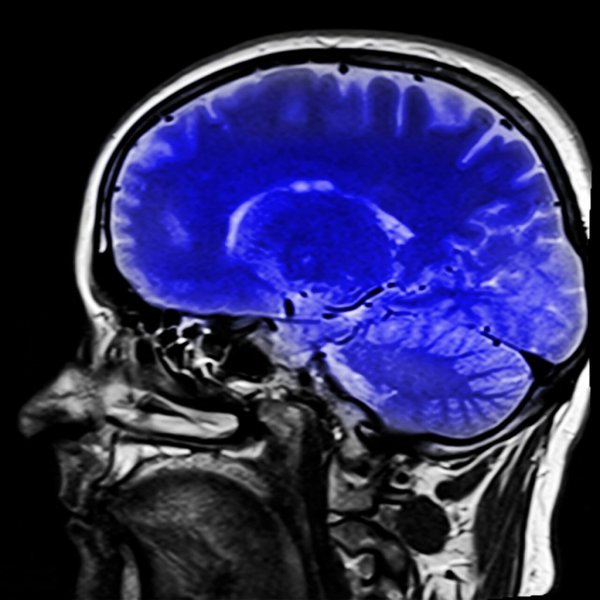

Er bestaan neurologische tests die artsen helpen om dit syndroom te diagnosticeren. MRI’s kunnen aantonen welk type beroerte opgetreden is. Dit zal hen helpen om te bepalen wat het is.